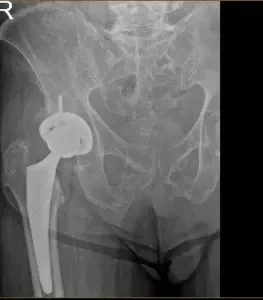

X-ray of a hip replacement

The hip was then relocated and the posterior soft tissue structures were then taken down and tied for future repair. A thorough lavage was given. Injection was given. Fascia was then closed with Eithibond.

Cutaneous tissues were closed with Vicryl. Subcuticular tissues were closed with 2-0 Vicryl. Skin was closed using Monoderm. Sterile dressing was then applied over the wound and the patient was then transferred to the postoperative care unit in stable condition.

Post-operative films show Right hip total arthroplasty, in good alignment, mild sacroiliac degenerative changes. Patient returned for a post operative appointment for staple removal and patients prognosis is good, due to an uncomplicated surgery. Patient is compliant with the outpatient physical therapy program, and is weight bearing fully bilaterally.